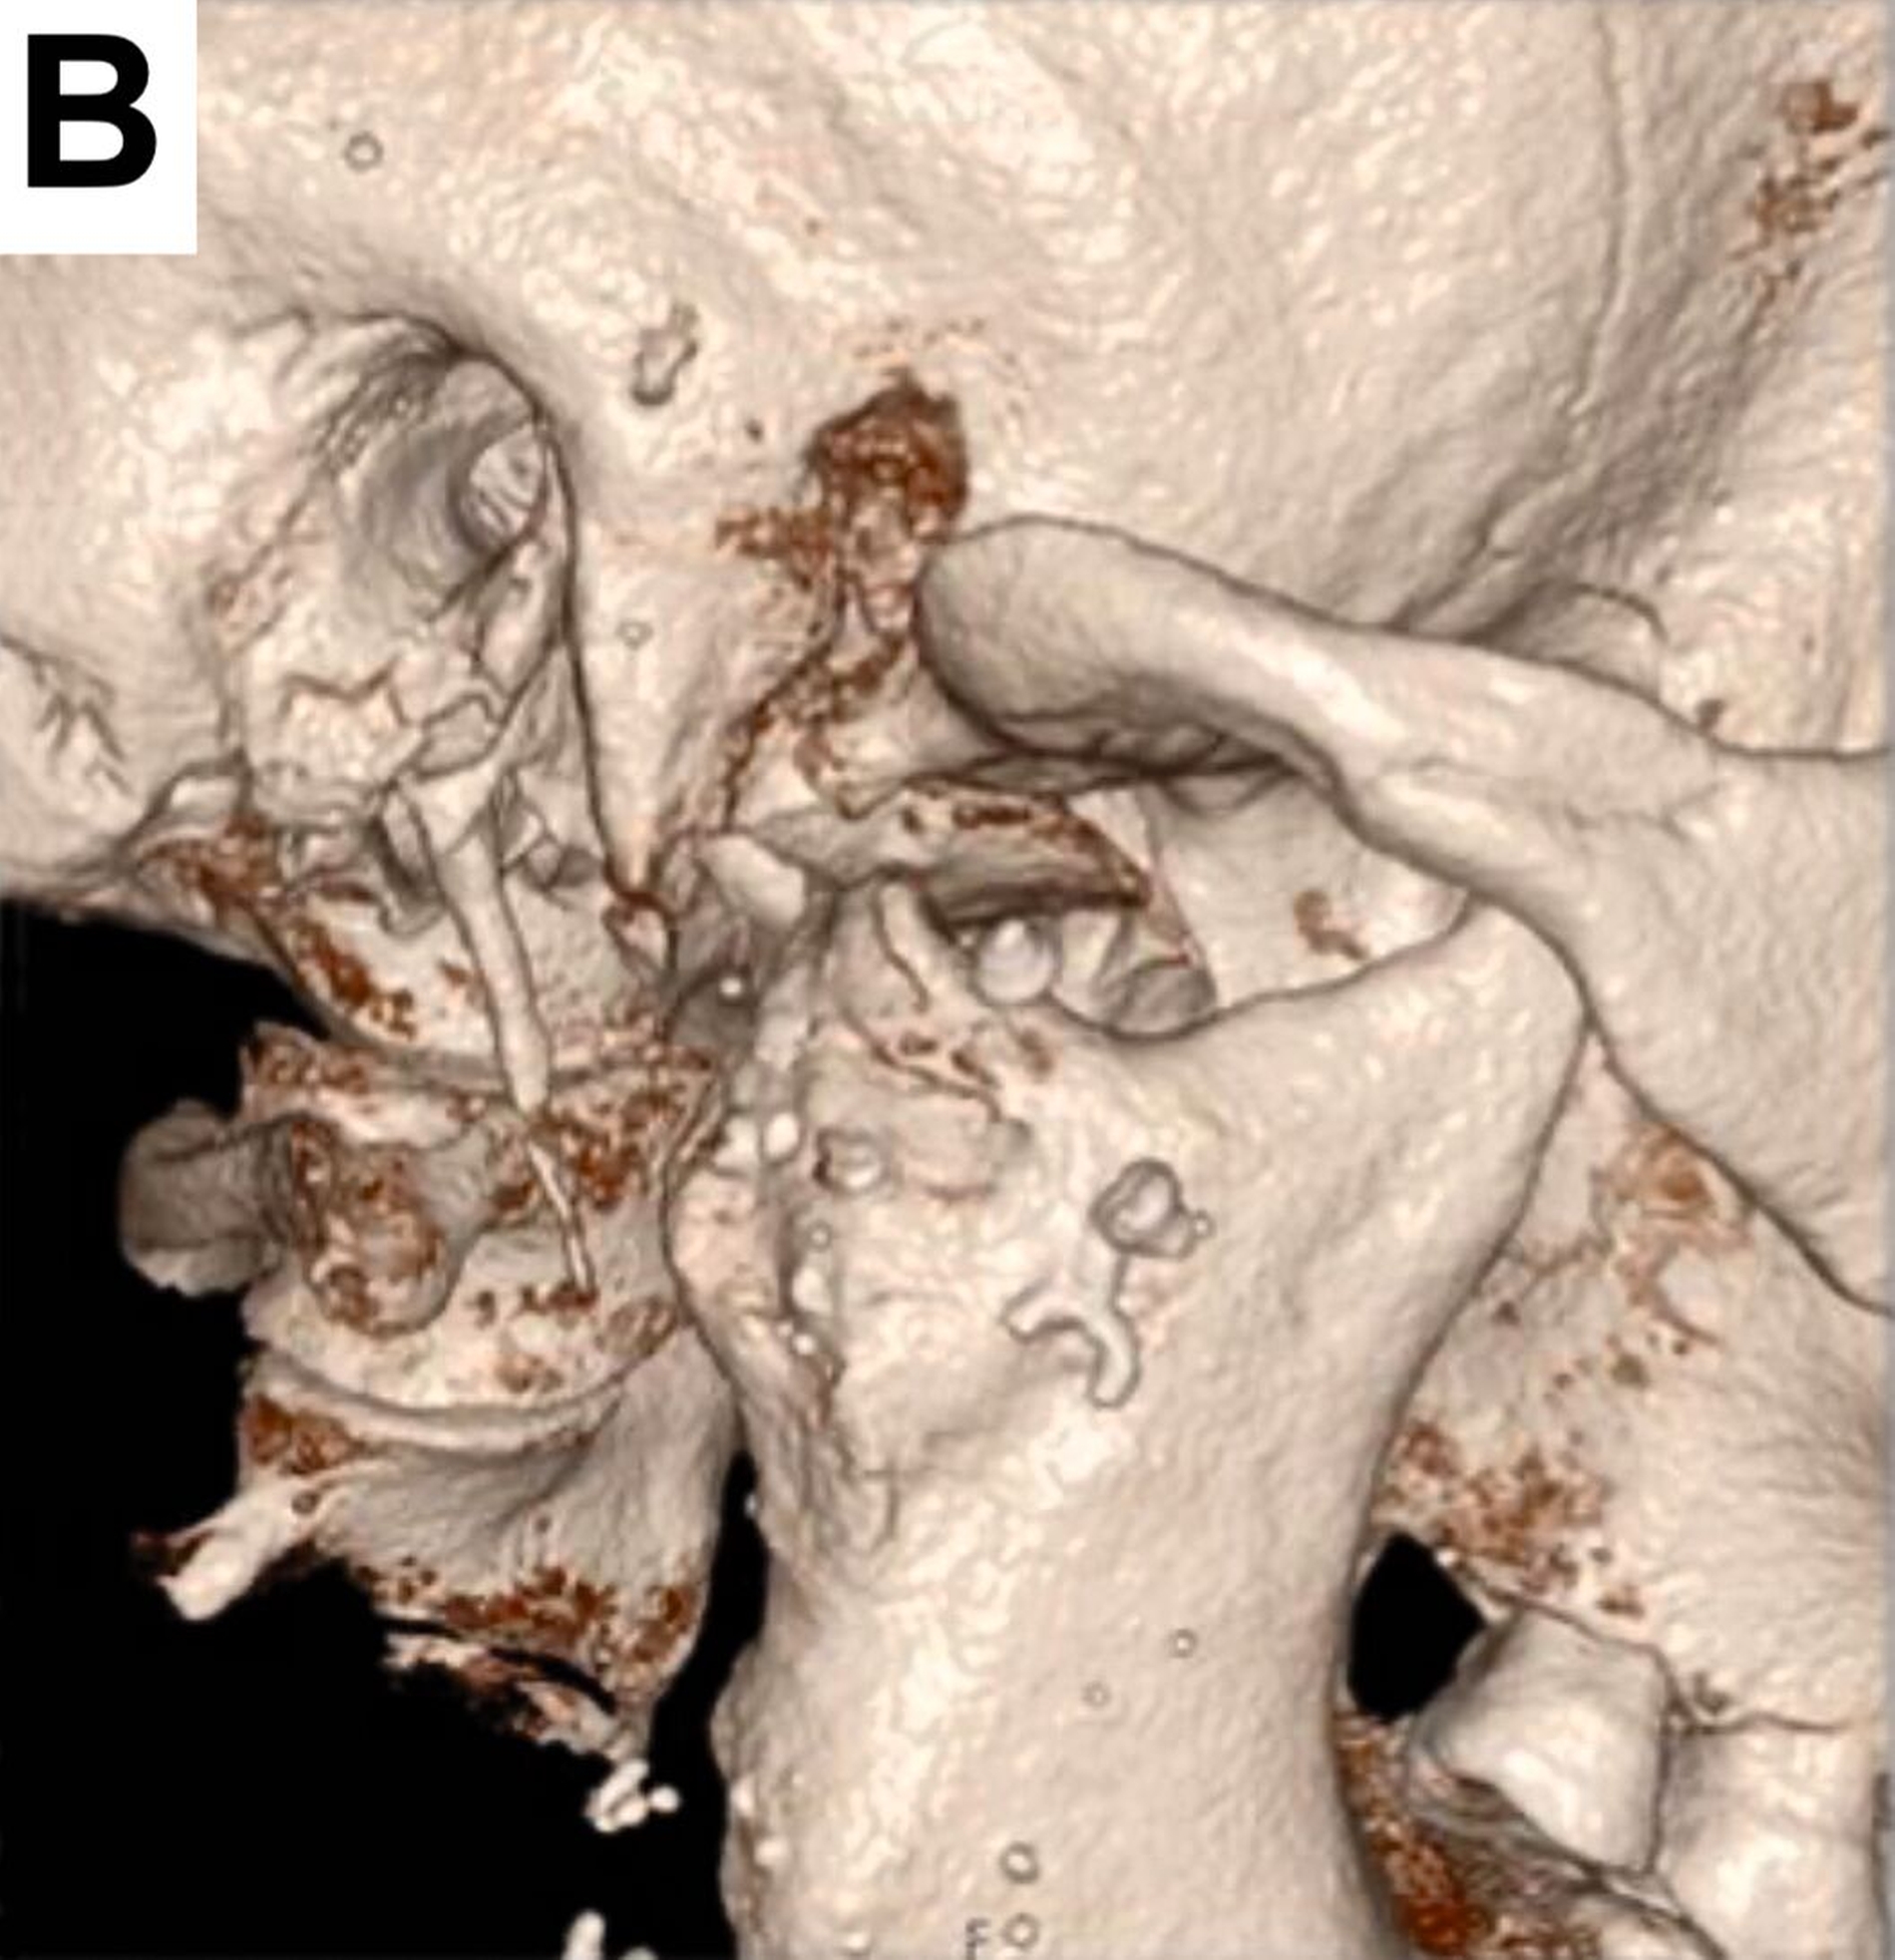

Bei der computertomografischen Untersuchung, die während der Patientenvorstellung durchgeführt wurde, wurde der totale Ersatz des rechten Kondylus durch die bereits beschriebene Endoprothese festgestellt, jedoch ohne Ersatz der Fossa mandibulae, was einem partiellen Kiefergelenkersatz entsprach. Das in situ befindliche Prothesenwerkstück hatte bereits zu einer nahezu vollständigen Erosion der mittleren Schädelbasis geführt (Abbildung 1).

Um eine weitere Dislokation nach intrakraniell zu vermeiden, erfolgte eine Woche nach der Erstvorstellung der Patientin die Entfernung des Endoprothesenwerkstücks (Abbildung 2).